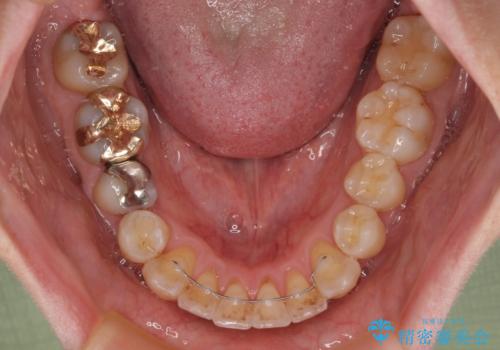

前歯のクロスバイト 目立たないワイヤー装置で矯正治療

- 前歯のクロスバイトを改善したいとのことで来院された患者様です。

マウスピース矯正では前歯の神経への負担が大きいことを懸念され、ワイヤー装置による矯正治療を行うこととしました。

舌の突出癖が認められたため、デコボコ改善に伴い前歯が前突する可能性があったため、舌のトレーニングをしっかりと行うよう指導しながら治療を進めることとしました。